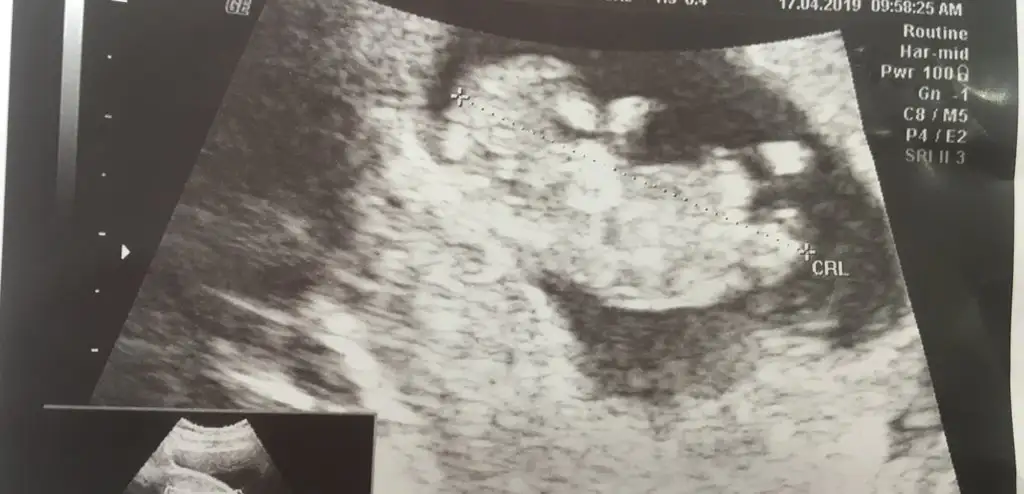

Ayy maşallah canım yaaa.Eki Görüntüle 2259482 Kontrolden çıktım kızlar çok şükür bir sıkıntı yokmuş